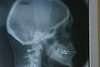

Décalage traité par gouttières

Début de traitement